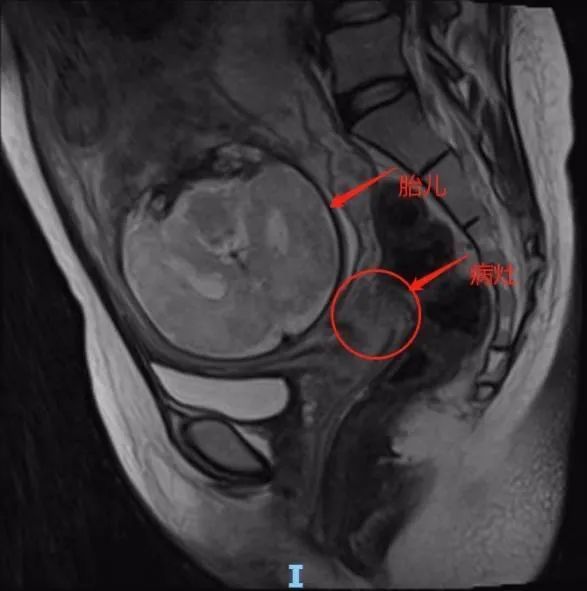

史文静带领团队查阅大量资料,了解国内外最近的诊治进展,多次组织妇产科与产科、儿科、麻醉科、放射科、外科、血液科等院内多学科团队人员充分讨论、反复研究,考虑如何有效治疗母体肿瘤的同时最大化保护胎儿安全,为小均制定个性化治疗方案,最后决定先做两个疗程的新辅助化疗,控制疾病进展,同时密切关注胎儿发育,尽量延长孕周再行剖宫产,并为小均施行宫颈癌根治手术。

国内外已有的实例表明,由于孕晚期胎儿大部分器官已发育完成,新辅助化疗的药物导致胎儿畸形或者发育异常的可能性较小,多学科团队的讨论结果给了小均极大的安慰。

孕33周时,广医二院妇产科联合多学科再次进行术前病历讨论和全院会诊,多方评估小均病情,讨论手术时机、方案、分娩及术式,分析可能出现的并发症及应对措施。考虑到手术时机已成熟,医护团队征得家属同意后决定为小均实施子宫下段剖宫产+宫颈癌根治术。